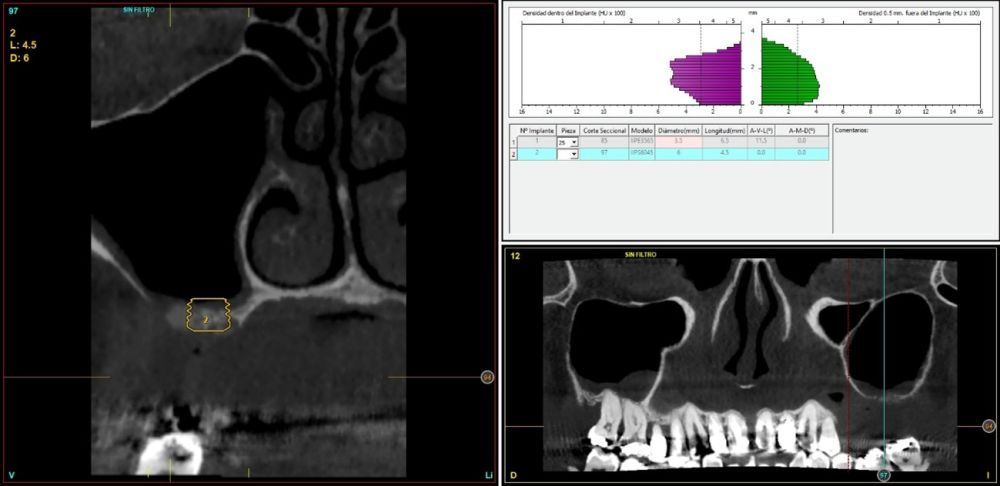

Fueron reclutados de forma retrospectiva pacientes en los que se llevase a cabo una inserción de implantes dentales de 4,5 mm de longitud en crestas óseas residuales de hasta 4,5 mm de altura con elevación de seno transcrestal, utilizando como material de injerto hueso autólogo obtenido del fresado y PRGF-Endoret, unido a la inserción directa con anclaje en la cortical desde junio de 2020 hasta septiembre de 2021. Antes de la colocación de los implantes, todos los pacientes fueron evaluados mediante modelos diagnósticos, exploración intraoral y un CBCT (Cone Beam Computed Tomography), cuyo análisis se realizó con un software especializado (BTI-Scan III), para conocer la altura exacta de la cresta ósea residual y la densidad, y poder adaptar en consecuencia el protocolo y el implante a colocar. Como protocolo preoperatorio, se administró una premedicación antibiótica con amoxicilina (2 g por vía oral) una hora antes del procedimiento, junto con paracetamol (1 g por vía oral) como analgésico. Tras la intervención, los pacientes continuaron con un tratamiento antibiótico de amoxicilina (500-750 mg por vía oral cada 8 horas, según el peso) durante cinco días. La colocación de los implantes fue realizada por un mismo cirujano utilizando la técnica de fresado biológico, caracterizada por bajas revoluciones y ausencia de irrigación, ajustando el procedimiento a la densidad y volumen del lecho óseo receptor para asegurar una adecuada estabilidad primaria del implante8-9.

En todos los casos se realizaron elevaciones óseas desde los 0,2 hasta los 1,3 mm. En la Figura 2 se observa la altura ósea inicial y final para cada uno de los implantes. Las posiciones más frecuentes de los implantes incluidos en el estudio fueron en 16 y en 26 con 33,3% respectivamente, y la menos frecuente en posición 27 (11,1%). Todas las posiciones se muestran en la Figura 3.

El tipo óseo más frecuente en las zonas de inserción de los implantes fue el tipo IV en el 46,7% de los casos con una densidad media de 263,89 Hu (+/- 134,82). En la Figura 5 se muestran las densidades de todos los implantes en función de la posición y el diámetro.